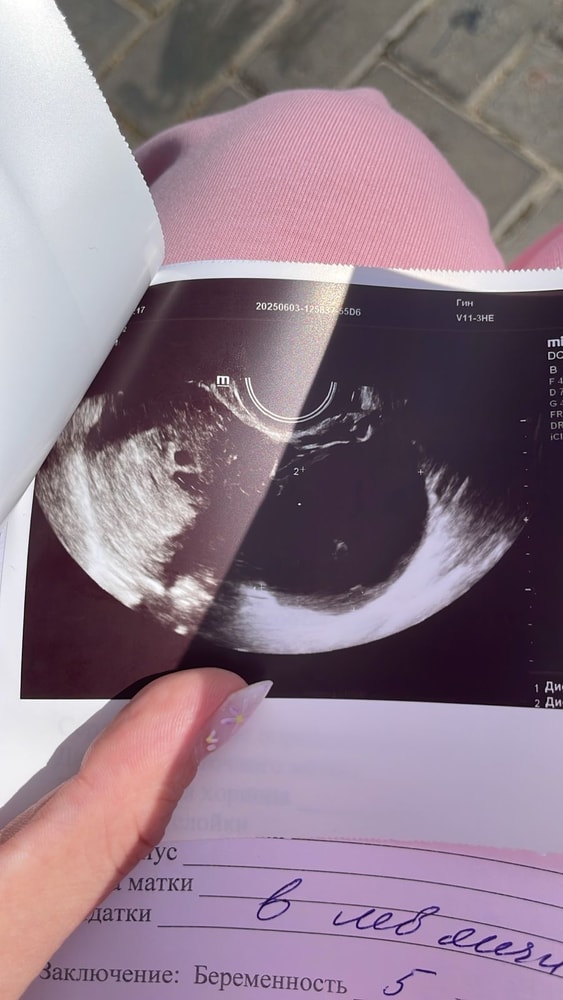

Ксения , на двух узи была вчера. На втором узи заподозрили 2е пя. Но так как срок 4-5 недель,еще не понятно.это узи из друго клиники,вчера напугалась,решила сходить перепроверить Изображение

Ксеня, тут уже реально похоже на 2 ПЯ, только контур почему тогда не сомкнут.. Может просто маленький срок и просто плохо видно , удачи вам!